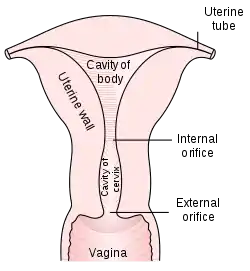

The cervix (pl.: cervices) or cervix uteri (Latin, "neck of the uterus") is the lower part of the uterus (womb) in the human female reproductive system. The cervix is usually 2 to 3 cm long (~1 inch) and roughly cylindrical in shape, which changes during pregnancy. The narrow, central cervical canal runs along its entire length, connecting the uterine cavity and the lumen of the vagina.[1] The opening into the uterus is called the internal os, and the opening into the vagina is called the external os. The lower part of the cervix, known as the vaginal portion of the cervix (or ectocervix), bulges into the top of the vagina. The cervix has been documented anatomically since at least the time of Hippocrates, over 2,000 years ago.

The cervix is part of the female reproductive system. Around 2–3 centimetres (0.8–1.2 in) in length,[3] it is the lower narrower part of the uterus continuous above with the broader upper part—or body—of the uterus.[4] The lower end of the cervix bulges through the anterior wall of the vagina, and is referred to as the vaginal portion of cervix (or ectocervix) while the rest of the cervix above the vagina is called the supravaginal portion of cervix.[4] A central canal, known as the cervical canal, runs along its length and connects the cavity of the body of the uterus with the lumen of the vagina.[4] The openings are known as the internal os and external orifice of the uterus (or external os), respectively.[4] The mucosa lining the cervical canal is known as the endocervix,[5] and the mucosa covering the ectocervix is known as the exocervix.[6] The cervix has an inner mucosal layer, a thick layer of smooth muscle, and posteriorly the supravaginal portion has a serosal covering consisting of connective tissue and overlying peritoneum.[4]

In front of the upper part of the cervix lies the bladder, separated from it by cellular connective tissue known as parametrium, which also extends over the sides of the cervix.[4] To the rear, the supravaginal cervix is covered by peritoneum, which runs onto the back of the vaginal wall and then turns upwards and onto the rectum, forming the recto-uterine pouch.[4] The cervix is more tightly connected to surrounding structures than the rest of the uterus.[7]

The cervical canal varies greatly in length and width between women or over the course of a woman's life,[3] and it can measure 8 mm (0.3 inch) at its widest diameter in premenopausal adults.[8] It is wider in the middle and narrower at each end. The anterior and posterior walls of the canal each have a vertical fold, from which ridges run diagonally upwards and laterally. These are known as palmate folds, due to their resemblance to a palm leaf. The anterior and posterior ridges are arranged in such a way that they interlock with each other and close the canal. They are often effaced after pregnancy.[7]

The ectocervix (also known as the vaginal portion of the cervix) has a convex, elliptical shape and projects into the cervix between the anterior and posterior vaginal fornices. On the rounded part of the ectocervix is a small, depressed external opening, connecting the cervix with the vagina. The size and shape of the ectocervix and the external opening (external os) can vary according to age, hormonal state, and whether childbirth has taken place. In women who have not had a vaginal delivery, the external opening is small and circular, and in women who have had a vaginal delivery, it is slit-like.[8] On average, the ectocervix is 3 cm (1.2 in) long and 2.5 cm (1 in) wide.[3]